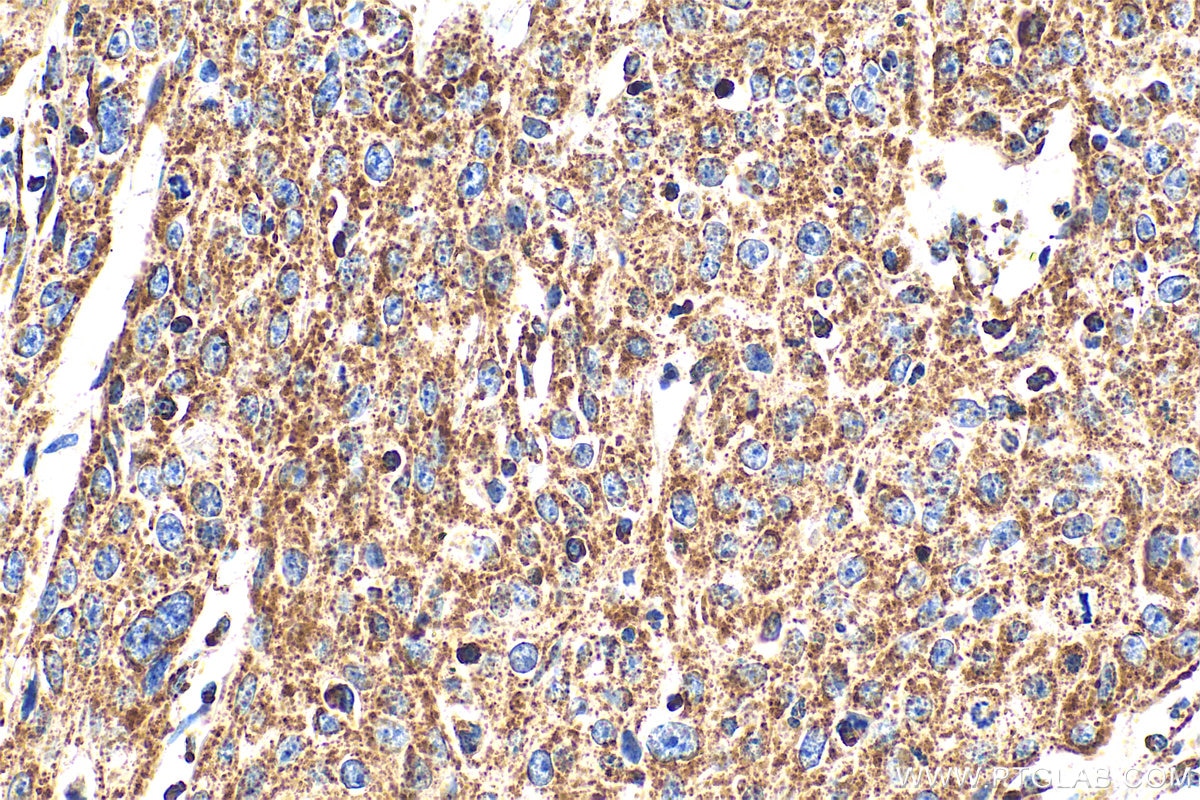

| Positive IHC detected in | human cervical cancer tissue, human breast cancer tissue Note: suggested antigen retrieval with TE buffer pH 9.0; (*) Alternatively, antigen retrieval may be performed with citrate buffer pH 6.0 |

| Immunohistochemistry (IHC) | IHC : 1:50-1:500 |

30663-1-AP targets SDHAF4 in IHC, IF/ICC, IP, ELISA applications and shows reactivity with human samples.